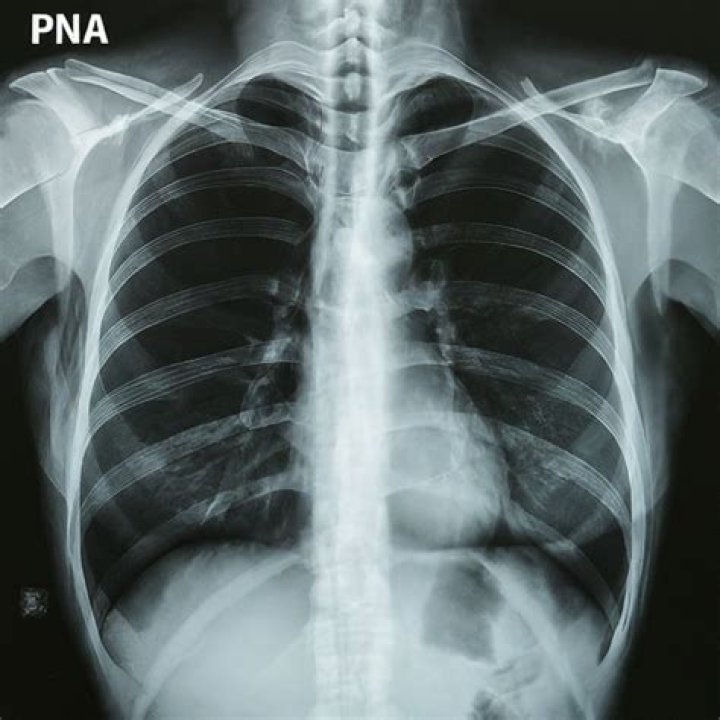

[pneumono- + -ia] ABBR: PNA Inflammation of the lungs, usually due to infection with bacteria, viruses, or other pathogens. Clinically, pneumonia is an